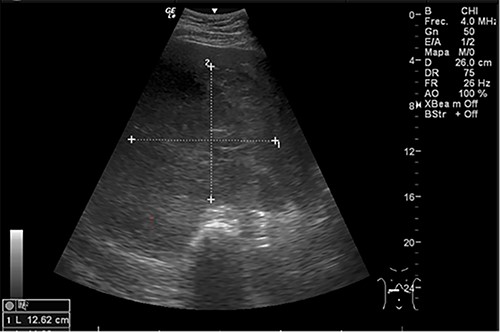

Examination revealed tachycardia, tachypnea, jaundice, dehydration, jugular vein distension, right lung hypoventilation, ascites, upper abdominal tenderness and bilateral lower limb edema. Laboratory workup highlighted neutrophilic leukocytosis, with WBCs exceeding 20 000/μl, along with an abnormal hepatic function panel. The latter showed hypertransaminasemia with ALT predominance over AST (344.7 U/L and 288.5 U/L, respectively), hyperbilirubinemia (10.01 μmol/L) and elevated values of ALP (909.1 U/L) and DHL (709.9 U/L). Of relevance, creatinine elevation (2.11 mg/dl), thrombocytosis (629 × 109/L) and positive D-Dimer (5780 ng/ml) were also noted, so acute kidney injury management and thromboprophylactic measures were initiated. A chest X-ray (CXR) showed a massive right pleural effusion (Fig. 1) and an abdominal ultrasound (US) revealed hepatomegaly with a right nodule (Fig. 2). After further evaluation, tomographic evidence of a right pleural effusion occupying 100% of the lung (Fig. 3) and a 20 cm hypodense, nodular lesion in the right liver (Fig. 4) were identified. These findings were suggestive of an ALA concomitant with an empyema. The patient was admitted into the intensive care unit and prepared for surgery.

CXR at admission: right pleural effusion occupying 90% of the lung.